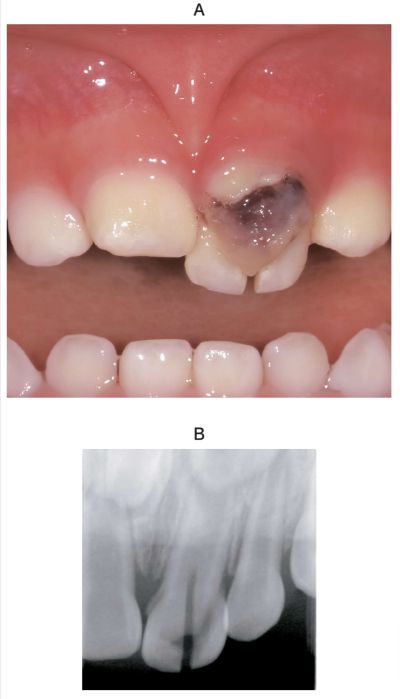

1歳6か月の男児。上顎乳前歯部の外傷を主訴として来院した。昨日、転倒し、上顎左側乳中切歯を受傷したという。初診時の口腔内写真とエックス線画像を別に示す。

適切な対応はどれか。1つ選べ。